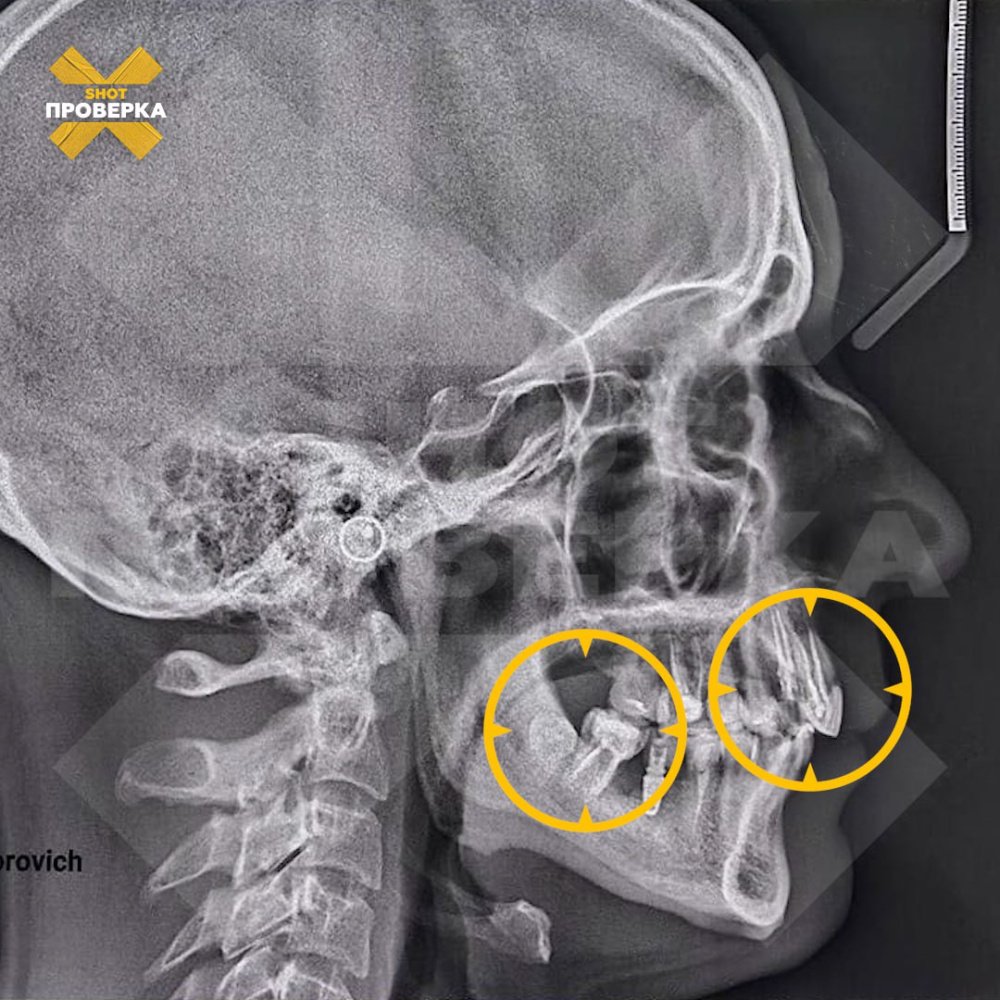

Однако вместо красивой улыбки они получили сильнейшее воспаление, гнойные нарывы, смещение челюсти и искривление зубов. Несмотря на жалобы пациентов, стоматолог довел процедуру до конца, а потом признал, что работа выполнена некачественно и пообещал исправить все недостатки. Однако ситуация не улучшилась.